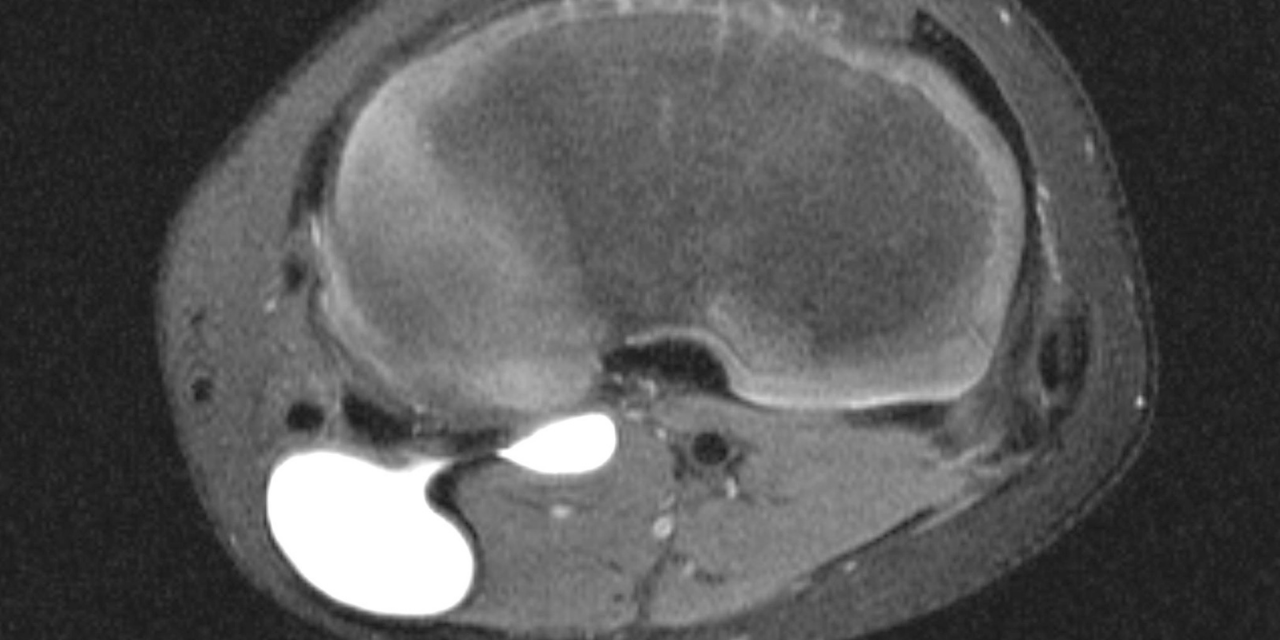

The popliteal cyst is most dramatically seen on the T-2 or fat-suppressed sequences, in which the cyst generally manifests well-defined increased signal intensity. As alluded to earlier in this article, the cyst is sited between the semimembranosus tendon and the medial head of the gastrocnemius. Figure 1 (a is a sagittal fat-suppressed image and b is an axial fat-suppressed image) demonstrates the position of the tendon (Sm) and the medial gastrocnemius (MGc). The communication between the cyst and joint can usually be ascertained by following sequential images in the coronal plane. Figure 2 is a fat-suppressed axial image that demonstrates a narrow neck of the cyst and the connection with the joint. In some instances, the cyst may be visualized as a soft tissue mass adjacent to the posterior aspect of the knee joint. This may be seen in the plain film x-ray (Figure 3) of a child with post-traumatic knee pain. The roughly crescentic soft tissue density is seen to extend from the distal femur inferiorly to the proximal tibial physis.